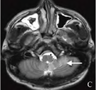

• 肾上腺嗜铬细胞瘤影像学表现韩毅力 / 副主任医师